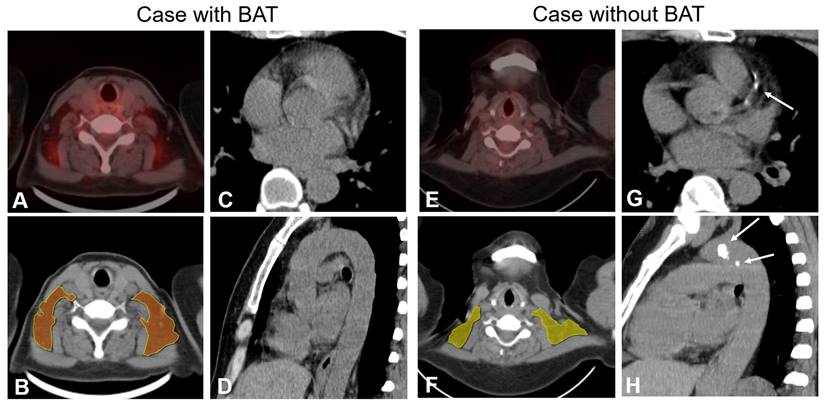

The BAT-RS group, as determined by the CT radiomics model, had lower odds of CAC and TAC compared with the non-BAT-RS group (CAC: 2.8% vs. 20.3%, p = 0.001; TAC: 19.4% vs. 39.2%, p = 0.009). The BAT-RS group had less CAC volume (4.1 ± 4.0 mm3 vs. 147.4 ± 274.3 mm3; p = 0.001) and a lower CAC score (2.8 ± 3.0 vs. 169.1 ± 311.5; p = 0.001). The difference in thoracic aorta calcification was more significant. There was lower TAC volume (301.4 ± 450.2 mm3 vs. 635.3 ± 1100.7 mm3; p = 0.007) and a lower TAC score (496.2 ± 132.6 vs. 749.2 ± 1297.3; p = 0.007) in the BAT-RS group compared to the non-BAT-RS group (Table 3). The values for cardiovascular calcification of each cohort are presented in Table S4. Examples of patients with and without CT radiomics based BAT and their cardiovascular calcifications are presented in Figure 3.

Figure 3

Examples of patients with and without BAT and cardiovascular calcification. PET-CT finding (panel A) and radiomics model (panel B) show BAT in bilateral supraclavicular depots in a 65-year-old female. Axial and sagittal CT images (Panels C and D) show no calcification of coronary arteries and thoracic aorta. PET-CT finding and radiomics model (Panels D and F) show no BAT depots in a 51-year-old female. Axial and sagittal CT images (Panels G and H) show calcified plaques both in the coronary arteries and thoracic aorta (white arrow).